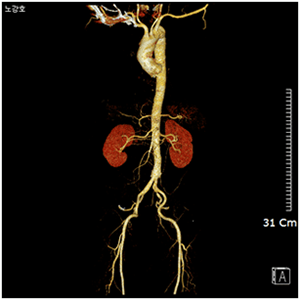

관상동맥 환자의 3D-CT

대동맥 환자의 3D-CT